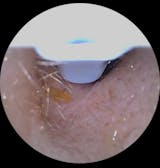

Ich bin wirklich überraschend begeistert von diesem Ohrenendoskop. Die Handhabung ist kinderleicht, die Verbindung zum Smartphone hat auf Anhieb funktioniert und die Bildqualität ist überraschend gut – gestochen scharf und detailreich. So konnte ich mir das Ohrinneres problemlos anschauen und erkennen, was los ist.

Besonders praktisch finde ich das schlanke Design und die integrierte Beleuchtung – dadurch sieht man selbst kleine Details sehr klar. Auch die mitgelieferten Aufsätze und Werkzeuge sind gut verarbeitet und machen die Anwendung noch einfacher und hygienischer.

Mit diesel Gerät kann ich selbst in regelmäßigen Abständen das Ohr vom gröbsten Ohrenschmalz befreien. Mit diesem Gerät tut es überhaupt nicht weh, die Aufnahmen der Kamera sind sehr gut. Mit etwas Geduld, Übung und Vorsicht kann man das Ohr wirklich sehr gut reinigen, ohne es zu verletzen. Ich kann das Produkt ohne Vorbehalte weiterempfehlen und würde es wieder kaufen.